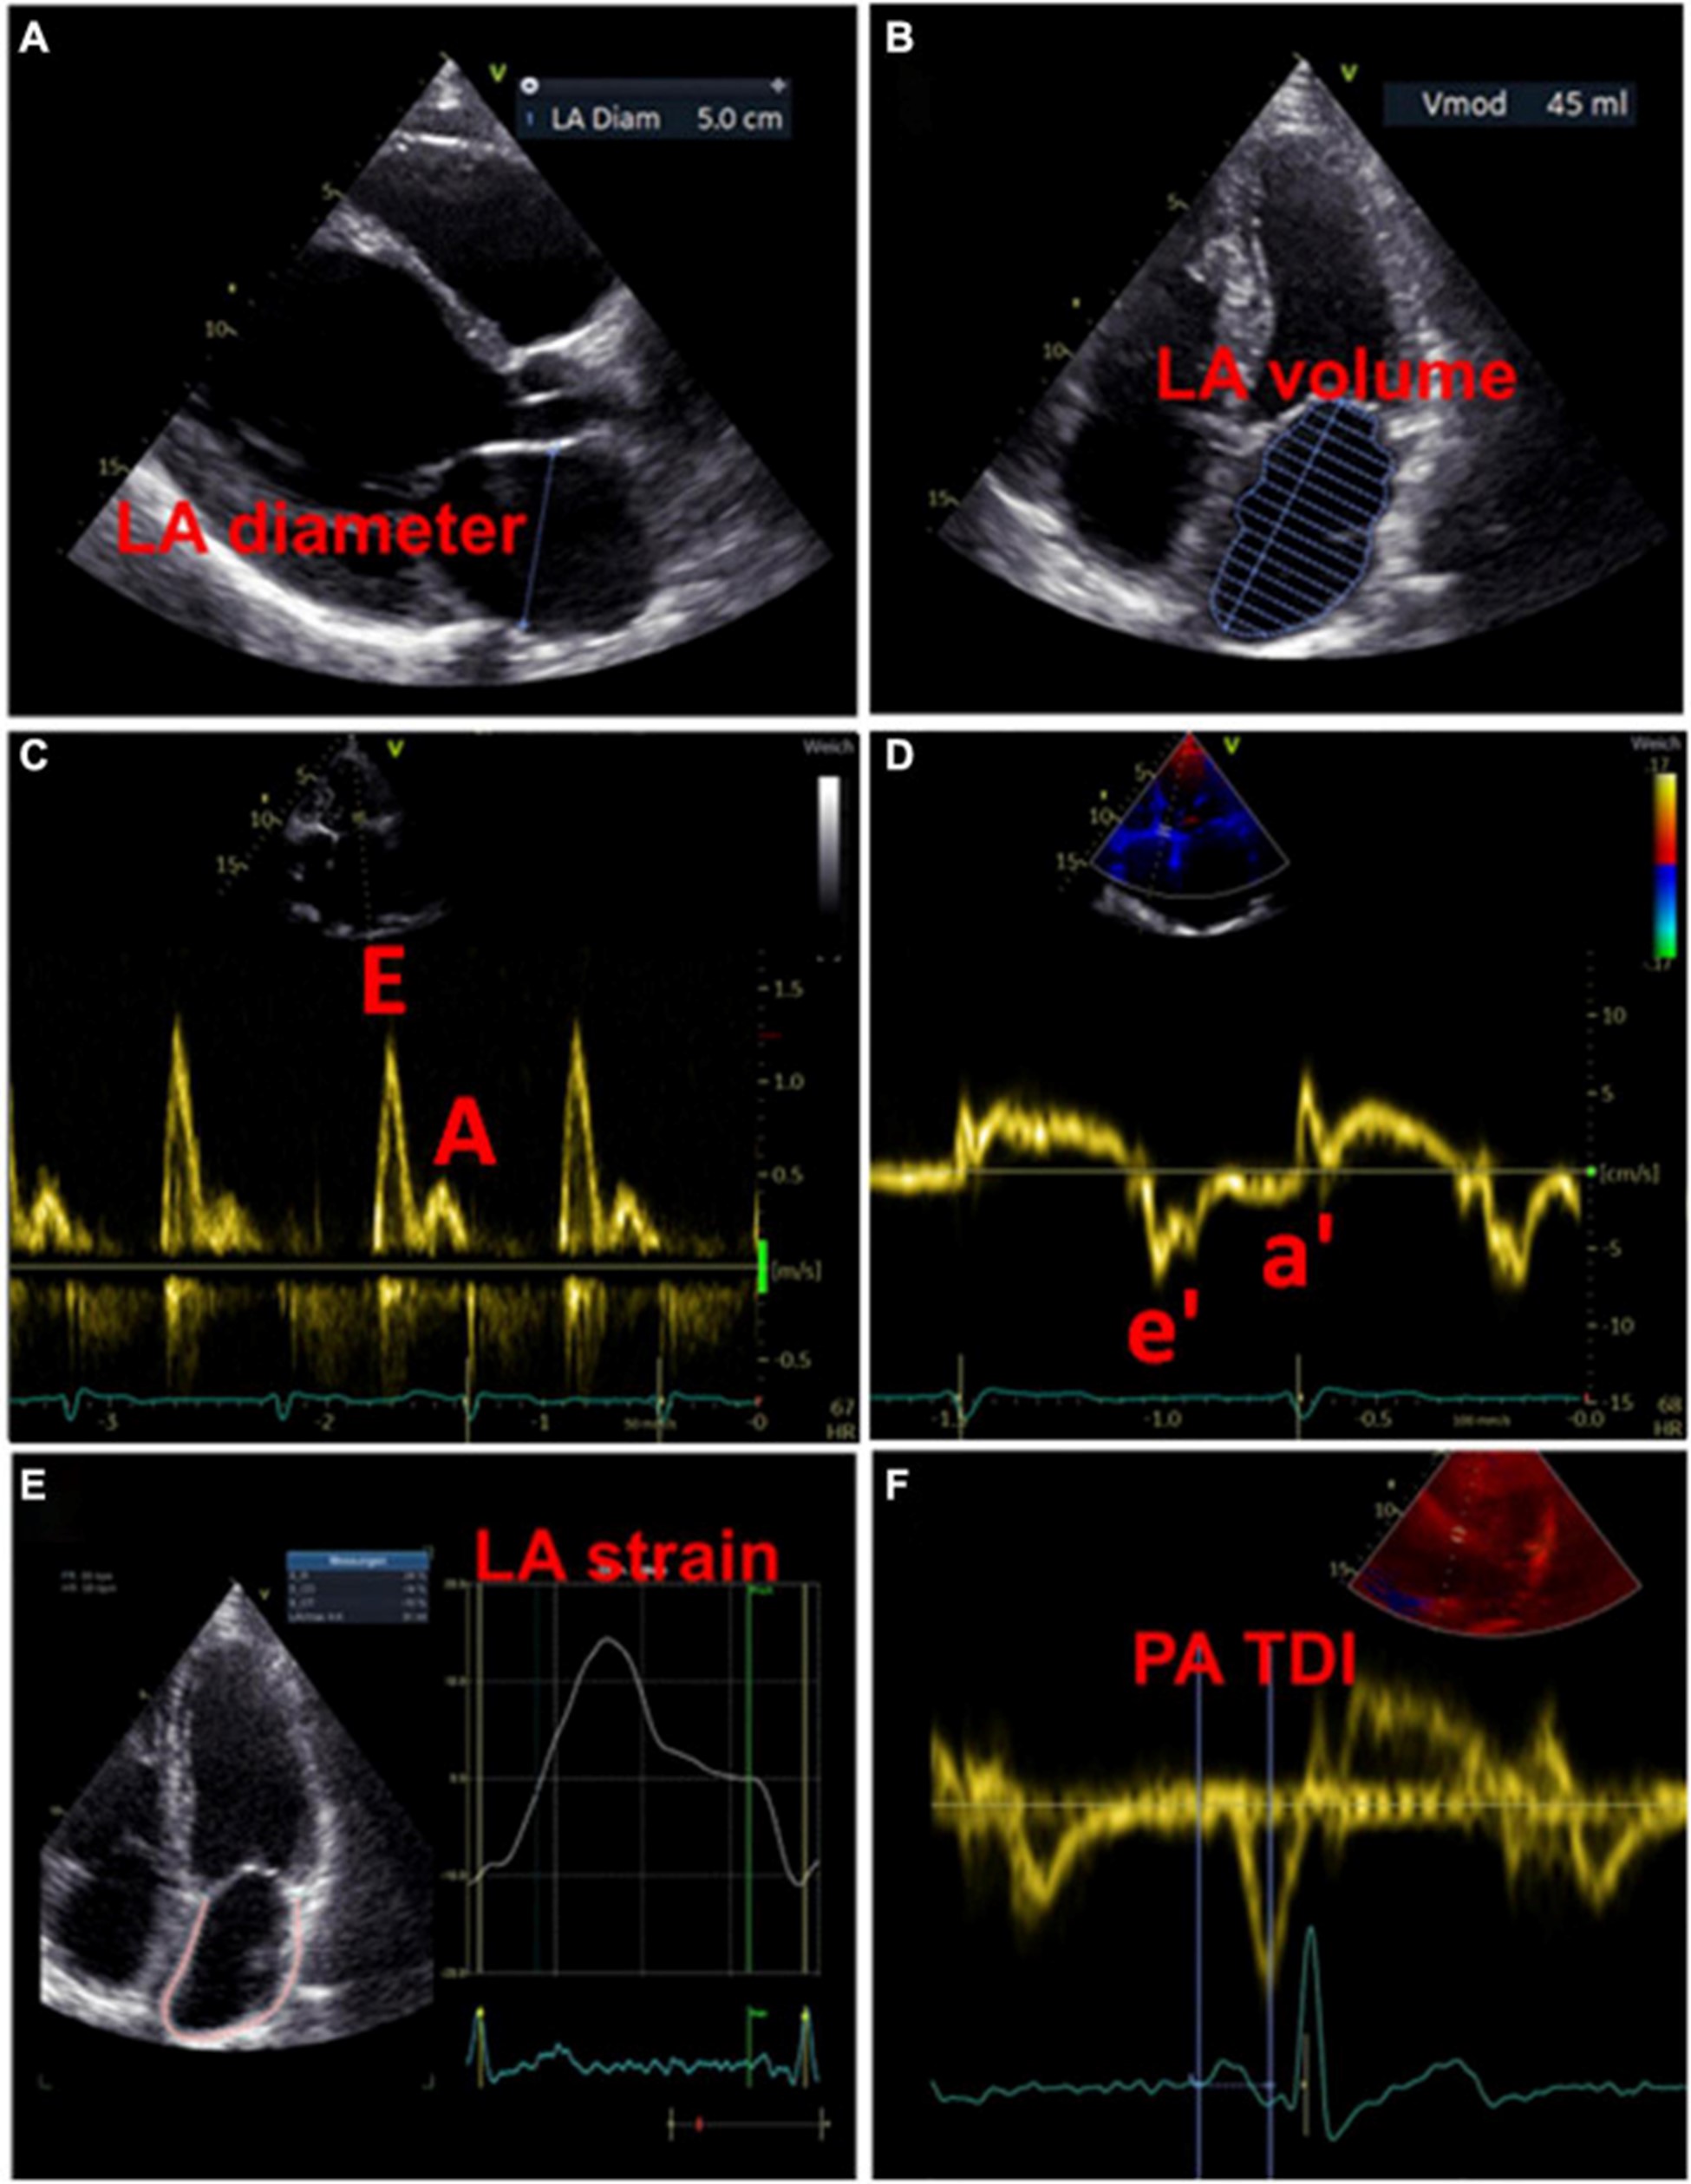

左心房大小

用于估计 LA 大小的一个广泛使用的参数是 LA 直径 (图 3A)。在 AFFIRM 研究中,增加的 LA 直径与复发性 AF 相关,但与卒中风险无关 。然而,一项荟萃分析揭示了较大的 LA 直径与中风和血栓栓塞事件的发生率之间存在关联 。此外,大 LA 直径和 LA 体积指数都被证明是主要不良心血管和血栓栓塞事件的预测参数,特别是在没有 AF 的年轻患者中 。LA 容积指数更精确,因此更适合估计心房大小(图 3B)。增加的 LA 体积指数已被描述为心肌功能障碍的潜在早期标志物,并且经常出现在 AF 患者中,在更高的 AF 负担中频率增加 。此外,与似乎没有预测作用的最大 LA 体积相比,最小 LA 体积与新发 AF 和主要不良心血管事件的发生率密切相关 ( 53 – 56 )。

图 3:用于检测左心房心肌病的超声心动图测量示例。(A)测量左心房舒张期的直径。(B)左心房舒张期左心房容积的测量。(C)左心室舒张期的经口流入曲线:第一波代表 E 波(血液被动流入左心室),第二波代表 A 波(左心房主动收缩)。(D)左心室心肌运动的组织多普勒成像,结合(C)心房功能和左心室舒张末期压力的测量结果。(五)左心房的应变分析。(F)测量从 P 波开始(作为心房电活动开始)到 a' 波峰值(心房收缩的机械反应)的 PA-TDI 间隔。

除了代表结构重构的 LA 大小异常外,心房功能评估可能为左心房心肌病的存在提供进一步的重要指标。LA 扩大和 LA 排空分数降低都是 AF 患者的常见现象,LA 大小与排空分数呈负相关 。最近,Eichenlaub 等人。评估了 AF 患者的 LA 排空分数,用于诊断左心房心肌病和预测 PVI 后心律失常复发 。LACM 定义为心内膜接触标测在 0.5 mV 阈值时LA 低电压区域 ≥ 2 cm 2 。LACM 患者的 LA 排空分数低于没有左心房心肌病的患者(27 对 41%,p < 0.0001)(43)。此外,LA 排空分数 < 34% 是 LACM(曲线下面积为 0.846)和 PVI 后心律失常复发的重要预测因素(57)。

多普勒超声心动图

此外,可以通过脉冲波多普勒测量和组织多普勒成像来评估 LA 功能。LA 功能受损可能提示 LACM,在使用多普勒超声心动图的研究中,这与 AF 和 AF 负担等临床结果等同。表格1)。

过去,已经研究了许多与二尖瓣血流和舒张期心肌运动相关的超声心动图参数与 LA 功能和临床事件的关联 。然而,尚未确定适合诊断左心房心肌病的参数和相应的临界值。

虽然 LA 传导功能(以二尖瓣 E 波速度为代表)随着 AF 负荷的增加而增加,但 LA 收缩功能(以二尖瓣 A 波速度和二尖瓣环组织多普勒 a' 速度为代表)具有相反的效果。

。早期 [E] 和晚期 [A] 舒张期充盈波的比率增加与 AF 风险之间存在关联。此外,描述了峰值 A 波速度和 AF 风险之间的 U 形关系 。

二尖瓣环“e”波速度降低和 E/e 比增加表明左室舒张功能受损。有证据表明后一个参数也适用于评估 LA 功能和压力 (图 3C、D)。

通过组织多普勒成像持续时间评估的总心房传导时间

通过组织多普勒成像持续时间评估的总心房传导时间,代表超声心动图得出的总心房传导时间,是结构和电心房重塑的吉祥标志,在窦性心律期间测量为 P 波开始之间的时间间隔在表面心电图上的导联 II 和超声心动图上左室侧壁的组织多普勒成像 (TDI) 跟踪上的 A' 波峰值 (图 3F)。PA-TDI 持续时间延长与节律控制干预后新发 AF、术后 AF 和 AF 复发相关 。在 AF 患者中,血栓栓塞风险的评估通过增加 PA-TDI 持续时间值得到改善。迄今为止,尚未建立 PA-TDI 持续时间的标准参考值。然而,如果每个超声心动图实验室通过常规获取 PA-TDI 值来确定自己的正常值,则可能会改善对 AF 相关结果的风险评估 。

斑点追踪超声心动图

近年来,斑点追踪超声心动图已成为通过评估组织运动来检测早期心肌变形的流行方法 。LA 应变和应变率成像提供了对心房功能重塑的见解。图 3E)。评估斑点追踪超声心动图效用的研究主要通过临床定义(例如,AF、AF 负担、AF 复发、血栓栓塞事件)或通过与电解剖标测中的异常发现进行比较来定义 LACM。表格1)。

经食道超声心动图

经食道超声心动图的一个重要优势是更精确地评估左心耳。关于经食管异常与左心房心肌病相关性的证据有限,LACM 主要通过延迟增强 MRI 确定纤维化来确定。经晚期钆增强 MRI 诊断,与没有血栓的患者相比,有 LA 附肢血栓的患者有更多的 LA 纤维化 。有自发回声对比的患者的 LA 纤维化程度甚至高于没有的患者。此外,高心房纤维化患者更可能在左心耳同时出现血栓和自发回声对比(70)。众所周知,LA/LA 附件血流动力学减少和 LA 大小增加是血栓和自发回声对比发生的危险因素 (图 4)。

图 4:经食道检查提示左心房心肌病的结果。(A)左心耳口的血流减少。(B)左心耳自发回声对比的证据。(C)左心耳血栓的证据。